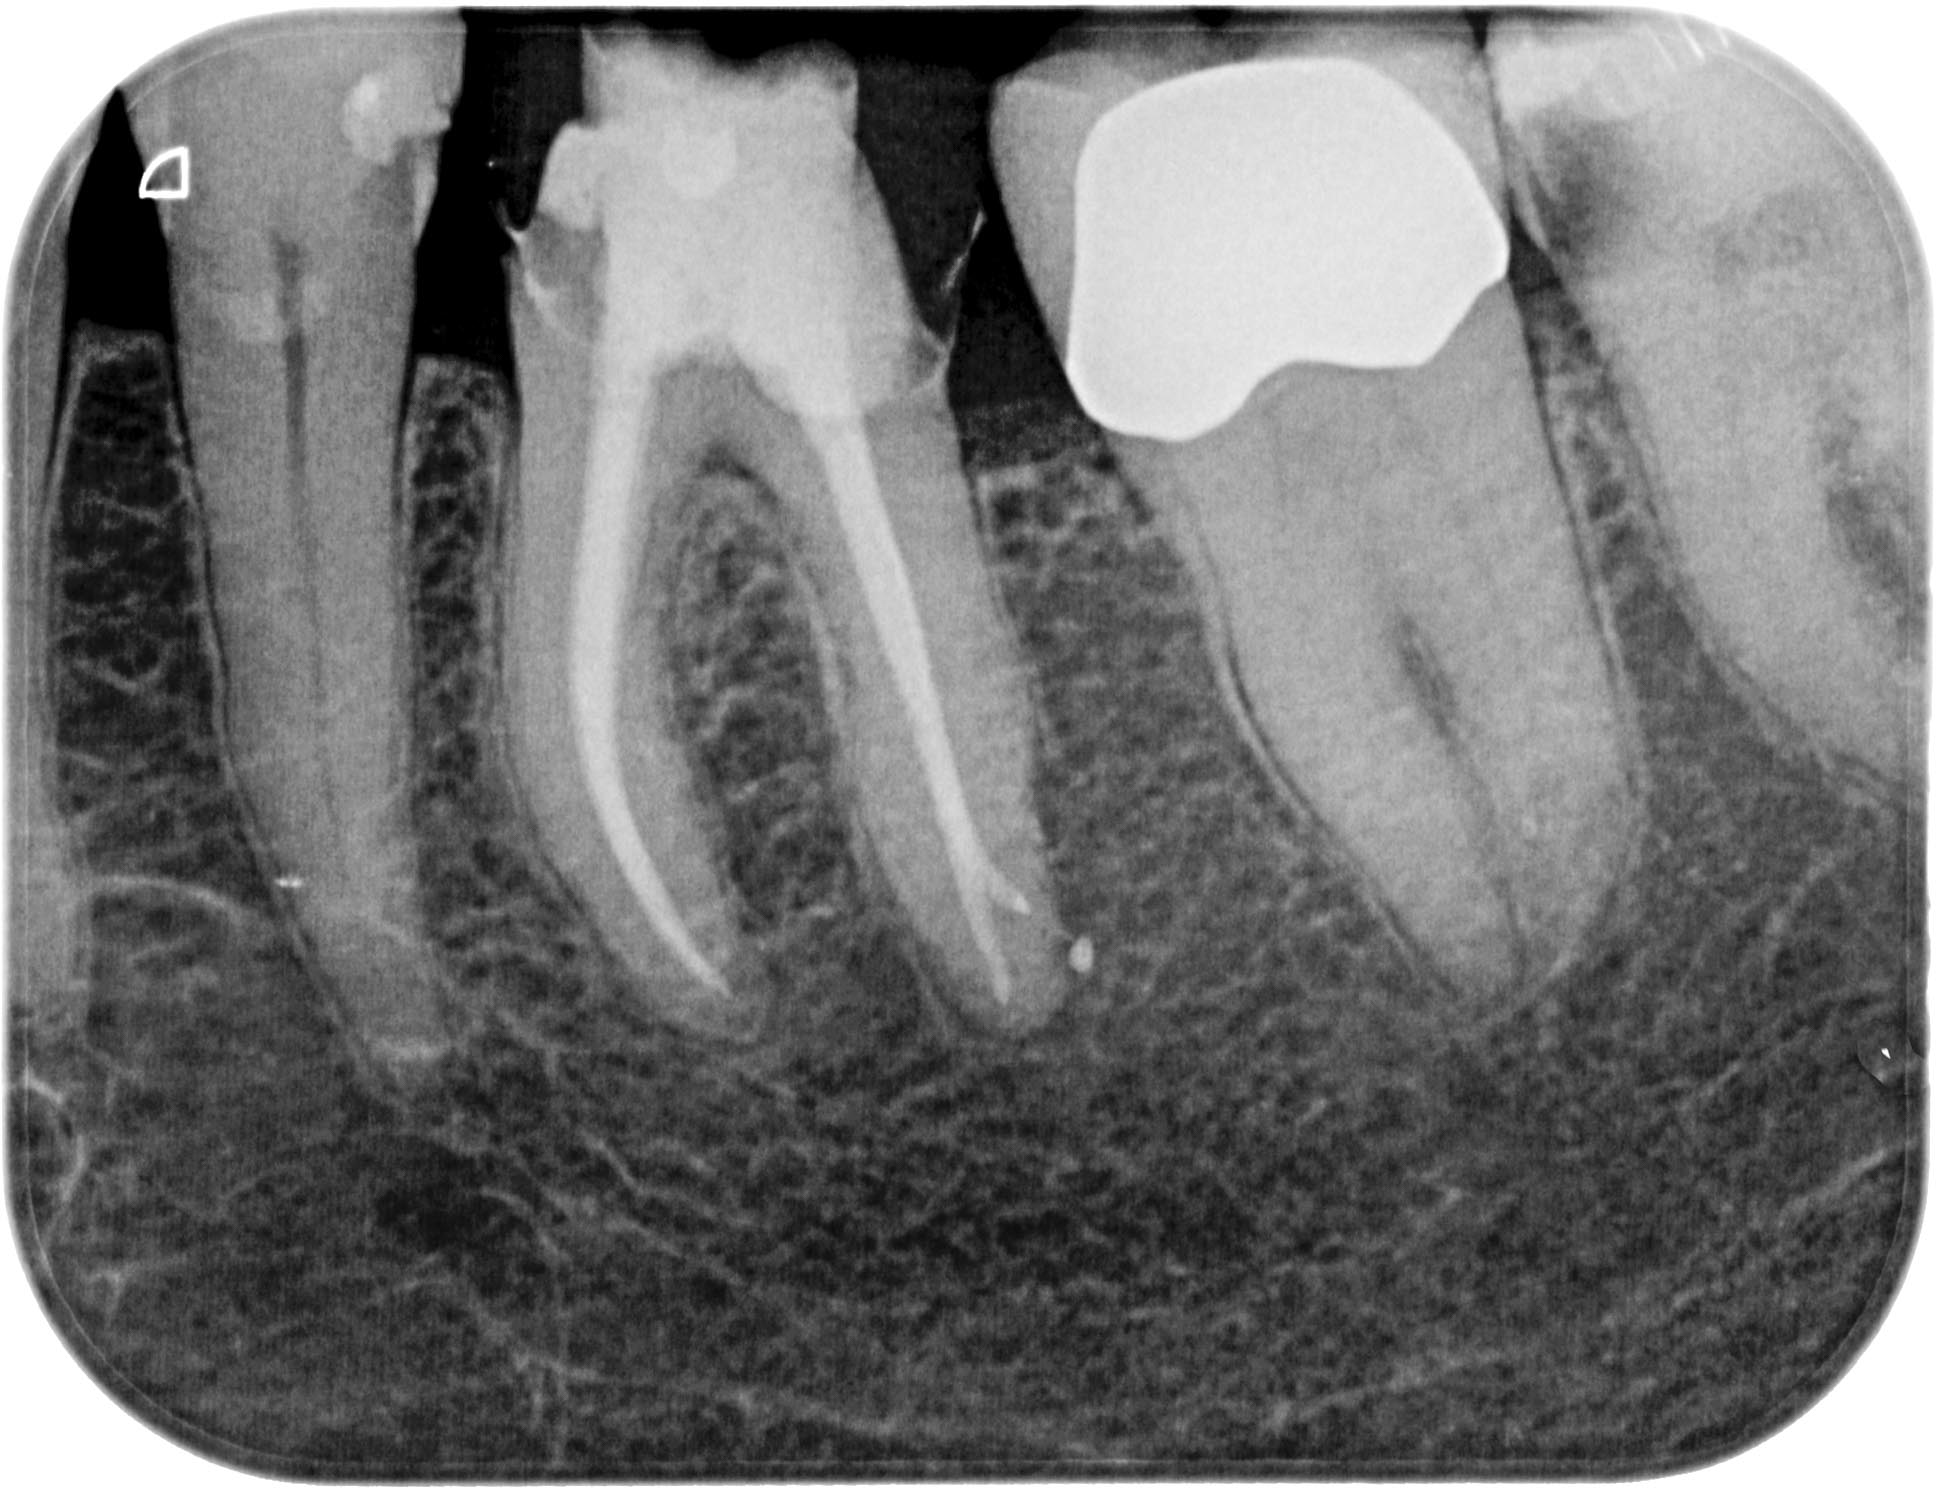

KSKrone6MonatepostWF-1-5 Veröffentlicht 24. September 2015 am 1938 × 1490 in Zuverlässige Endometrie bei Metallkronen – aber auch – Wäre das nicht eine sinnvolle neue Rubrik für WURZELSPITZE ? Zahn 36 6 Monate post WF